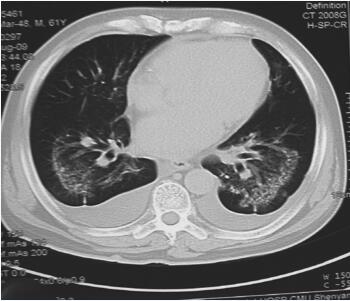

图2-3 胸部CT检查(入院第3天)

正常值5倍;⑧无心肌生化标记物结果情况下,新发生的存活心肌的丢失的影像学证据伴心肌缺血症状;⑨尸解病理发现急性心肌梗死。